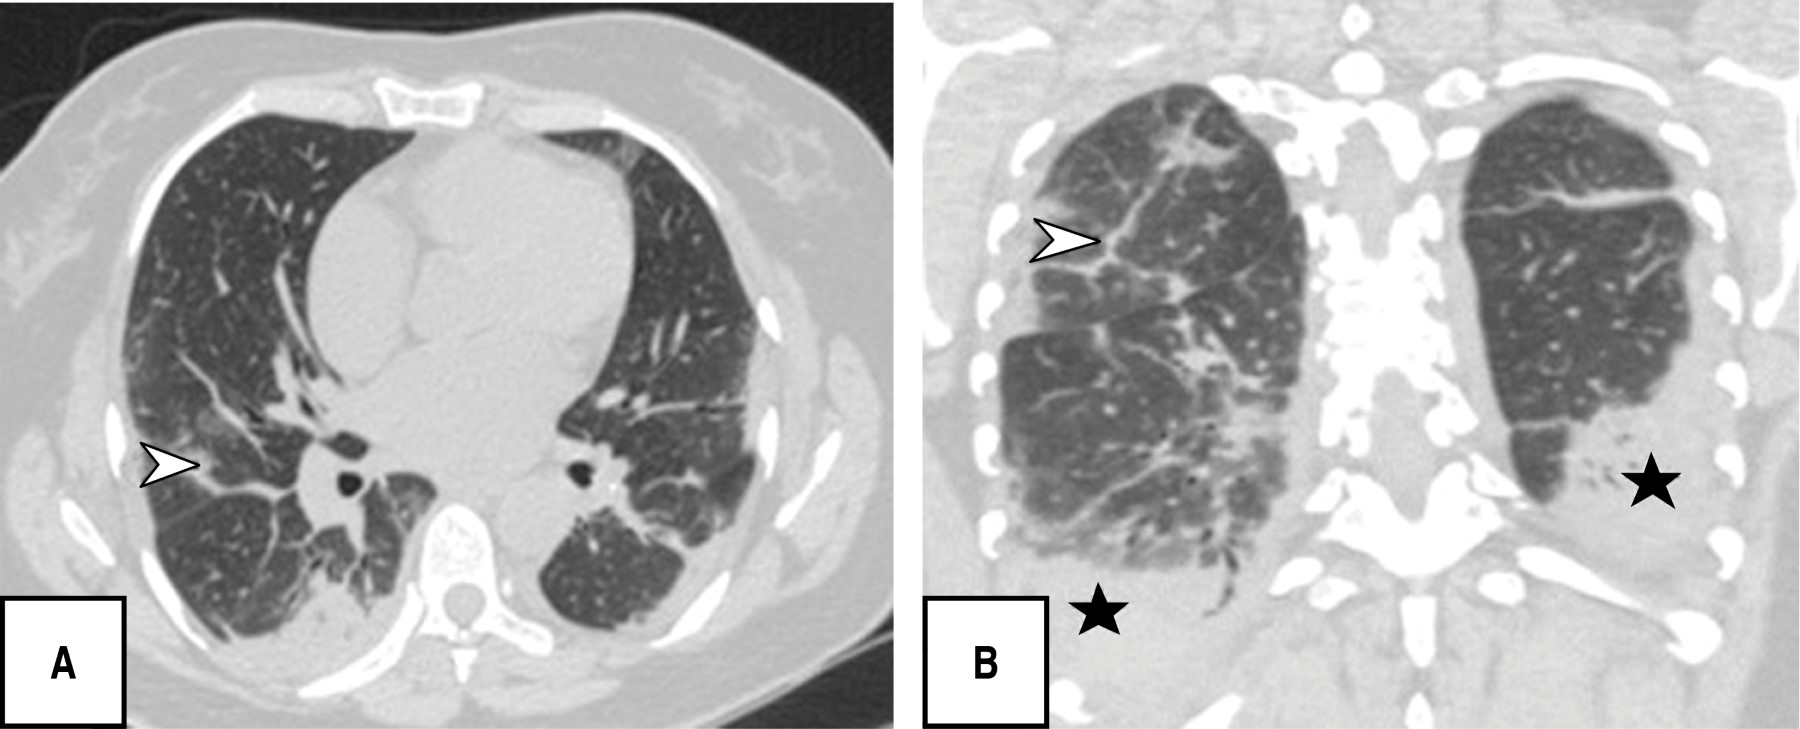

During the tomographic evaluation, the most frequent pulmonary patterns were: cobblestone pattern (120 [80.5%]), pleuroparenchymal bands (118 [79.2%]) and ground glass pattern (110 [73.8%]), reticular pattern (82 [55%]), and in lower percentage vascular dilatation (56 [37.6%]) and consolidated pattern (52 [34.9%]) (Figures 1, 2, 3 and 4).

Each patient was found to have five of five lung lobes affected, 144 (96.6%), with a total percentage of involvement of 26-49%, (96 [62.4%]); the most characteristic distribution of lung involvement was central and peripheral (86 [57.7%]), and without segment predominance (86/57.7%) followed by localization in posterior segments (59/39.6%), all with statistical significance (p < 0.05). The PATPAS severity score presented by the patients was moderate (93 of 149 patients [62.4%]).

Eighty-six patients were identified with positive laboratory tests by PCR-RT, which were included within the CORADS 6 category (cases already confirmed by laboratory plus typical finding by CT), in addition patients confirmed by antigen test were included, thus adding up to a total of 143 out of 149 (93%); only six patients had a negative laboratory test by PCR-RT and antigen, which were categorized as CO-RADS 5 with very high suspicion of presenting the disease by typical findings by CT AR (p < 0.05).

Soriano et al. reported that the presence of ground-glass opacities, reticular pattern, cobblestone pattern, subpleural lines, pleural thickening and fibrosis were more frequently found in the intermediate/progressive phase, especially in the advanced phase; similarly we observed a significant correlation (Pearson's index of 0.65) between the predominant pattern and the progressive phase of the disease.23 The CT scores of the progressive stage group were significantly higher than those of the early stage group; however, in this study there was no statistical significance between CT pattern and severity score.